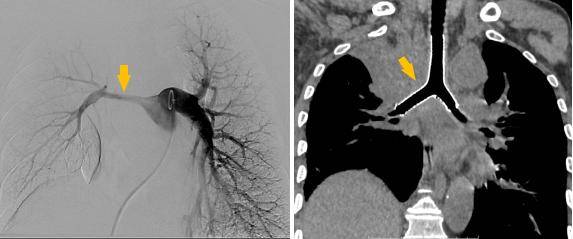

术前受压变窄的右肺动脉和中央气道